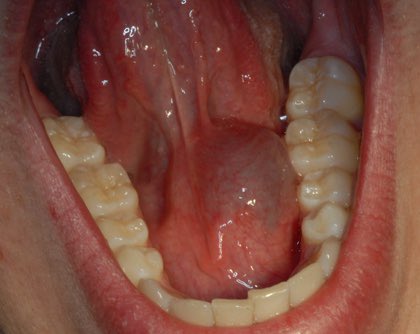

والغدة التي تحت اللسان نادر تأثرها بالتهابات او أورام وأكثر شي يؤثر عليها هو الكيس اللعابي Ranula